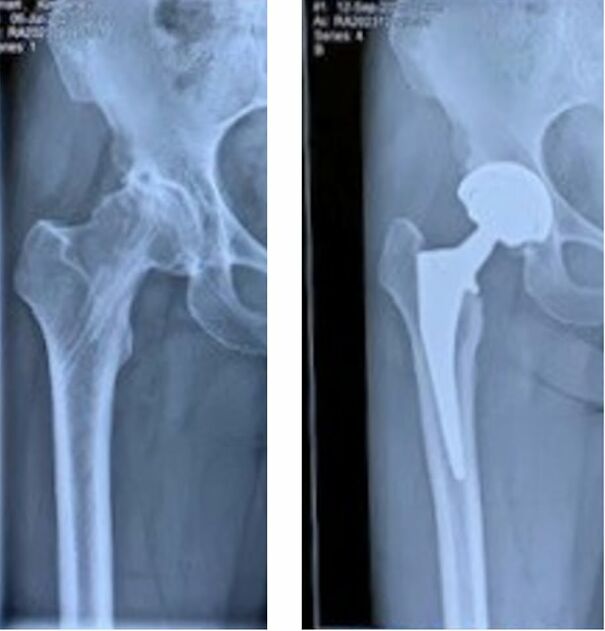

Before And After Hip Replacement Surgery

Had a hip replacement and I can tell you the pin is the least of it. The surgeon basically cuts through most of your glute muscles to get to the joint. Then I think they dislocate the joint to be able to saw off the end of the femur and jam that spike in there. I refuse to watch a video of the surgery - I'll throw up.... The first couple of weeks my leg felt like someone had twisted it all around like a Barbie doll leg. It took almost a year before I could do a single feeble lunge Hip-replac...1d2320.jpg

My Dr went through the front, I felt completely healed and had no restrictions within months.

Load More Replies...What isn't visible in the photo is how d**n deep that pin goes into your bone and how long it is. My mom had hip replacenent surgery and even if it went well, it was really slow and painful healing. After seeing the photo where the pin reached almost down to the knee, it's no wonder why it's so painful ans slow-healing.

Both hips replaced. A little uncomfortable for the first 2 weeks, pain meds took care of most of that. A couple of common sense restrictions, like don’t cross your legs, the first few months. I am very glad I had both done. I’m totally back to normal now, no pain, no restrictions. I’m commenting so that people know it’s not that bad. I’ve read that some people didn’t have the same results I did. I would check out all your orthopedic surgeons to find who’s the best available.

Load More Replies...Wire because bone split when the femoral component was driven in.